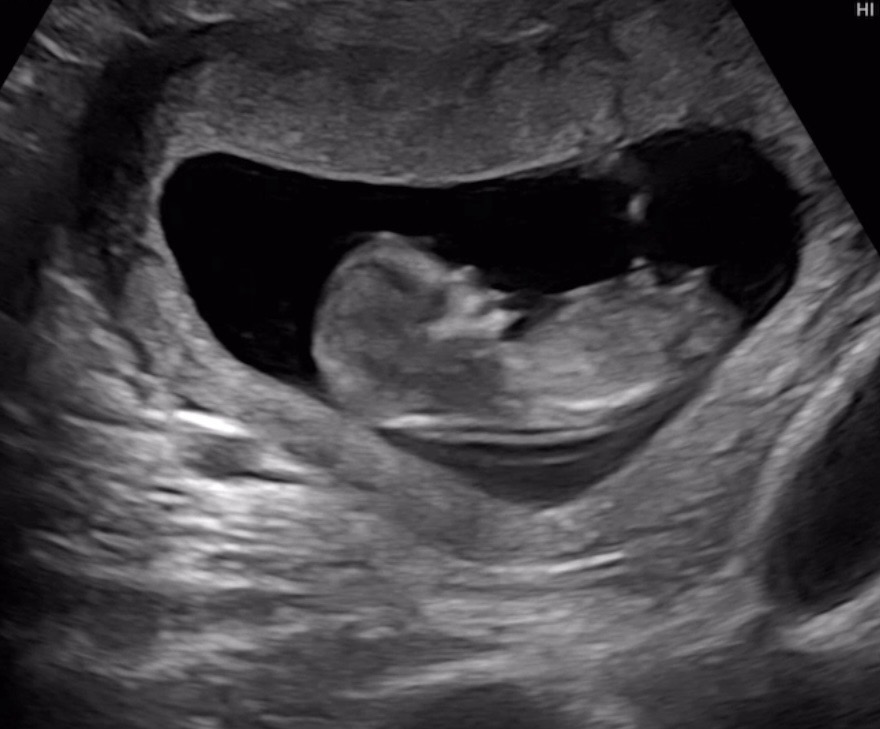

저희 애기 성별 예측부탁드려요👼🏻

태몽이나 뭐 미신으로 하는 성별 확인법은 아들이고 앞으로 배만 나오는건 딸 같다고 하구ㅜㅠ 다음주에 가면 이제 성별 알 수 있을거는 같은데 과연 저희 애기 성별은 뭘까요~?!🥲 투표 부탁드려요ㅜㅜ